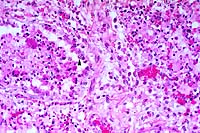

- Case 18-2. Spinal cord. Neuronal degeneration, necrosis,

and loss is responsible for fragmentation & collapse of spinal

cord gray matter. At 20x, neuronal cytoplasm has increased eosinophilia

and nuclei are karyorrhectic.

- AFIP Diagnosis: Spinal cord, ventral gray horns: Neuronal

necrosis, bilaterally symmetrical, breed unspecified, porcine.